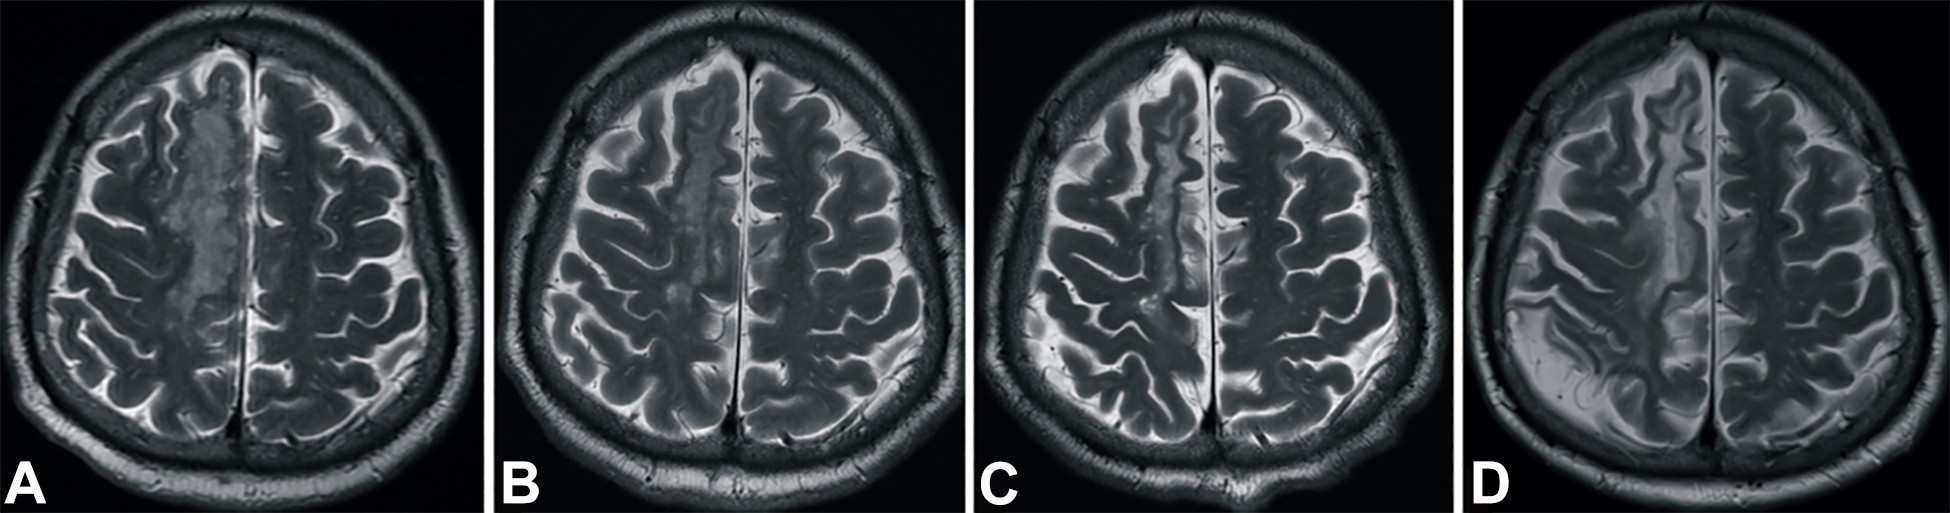

梗塞發(fā)生后2小時、8 天、3 個月和 6個月獲得的T2加權(quán)圖像顯示右側(cè)放射冠白色強(qiáng)度增加(圖3A-D)。

中風(fēng)后2小時和輸血后6個月獲得的T2加權(quán)圖像。

圖3.中風(fēng)后2小時和輸血后6個月獲得的T2加權(quán)圖像。(A)中風(fēng)后2小時,(B) 輸血后1天,(C) 輸血后3個月,(D) 輸血后6個月